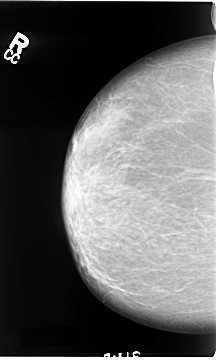

B_3064_1.RIGHT_CC

RIGHT_CC LINES 4672 PIXELS_PER_LINE 2808 BITS_PER_PIXEL 12 RESOLUTION 50 NON_OVERLAY